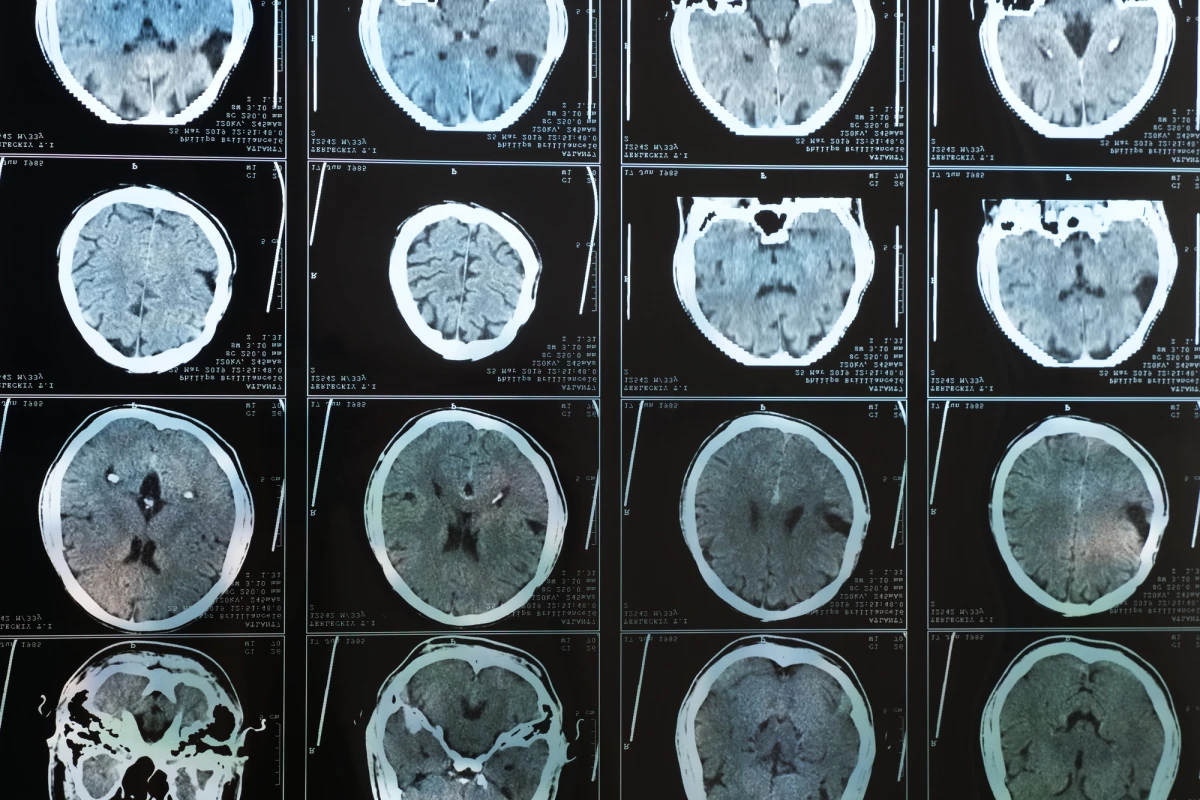

تصویربرداری های جدید نشان میدهد چاقی خطر ابتلا به آلزایمر را افزایش میدهد

مطالعه تصویربرداری از مغز سرنخ این موضوع را نشان می دهد که چاقی چطور می تواند خطر ابتلا به آلزایمر را افزایش دهد.

داده های جدید حاصل از یکی از بزرگترین مطالعات تصویربرداری از مغز در نوع خود، ارتباط مستقیمی بین افزایش وزن بدن و کاهش گردش خون مغزی نشان داده است.با تصویربرداری از مغز در این تحقیق بینش بیشتری در مورد پیوندهای بین آلزایمر و چاقی نشان می دهد،حفظ وزن مناسب می تواند به طور مستقیم خطر ابتلا به زوال عقل و الزایمر را کاهش دهد.

در مطالعه جدیدی که توسط تیمی از محققان آمریکایی انجام شده است، اسکنهای مغزی از بیش از 17000 فرد برای بررسی ارتباط بین وزن بدن و جریان خون مغزی مورد بررسی قرار گرفت. الگوهای شناسایی شده قابل توجه بودند، و جریان خون در تعدادی از مناطق مغز نسبت به شاخص توده بدنی بیشتر کاهش داشته است.